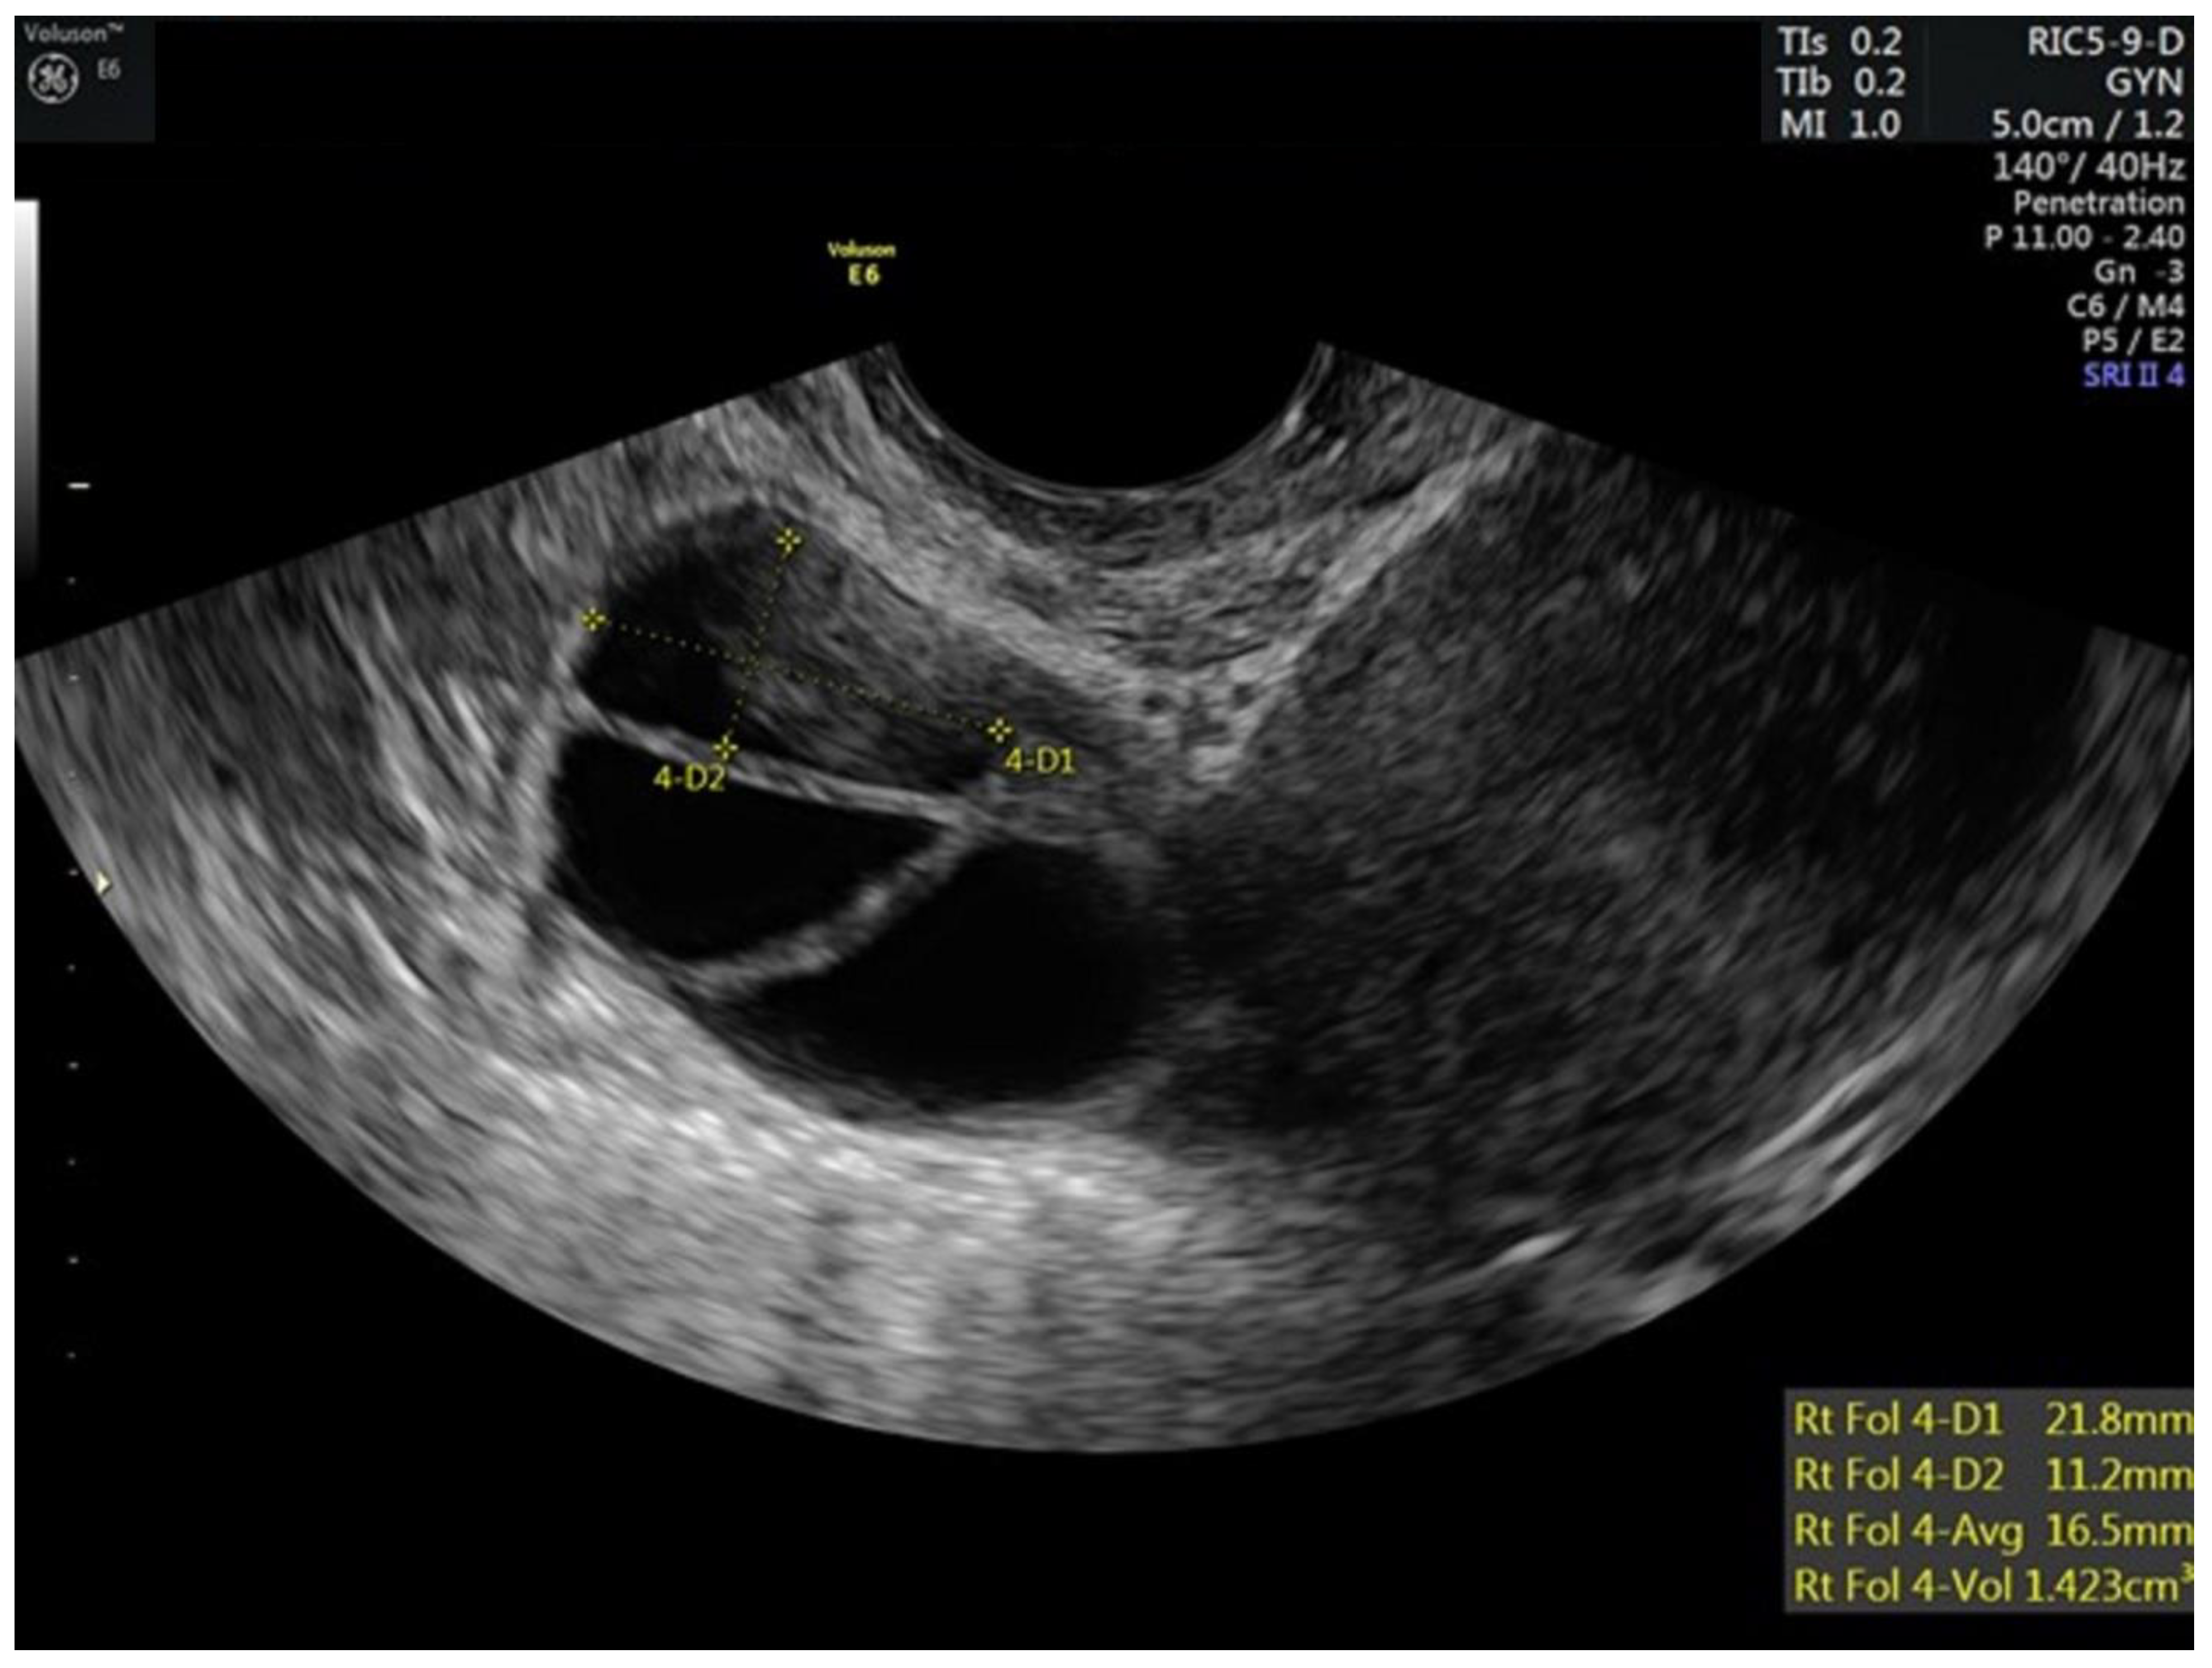

| 10 | 5 | 40 | 100 | 75 | 250 | 172 | 0.6 | 19,17,17,13,12,12,9,6 | 18,17,16,16,13,4 | 5.3 | ||